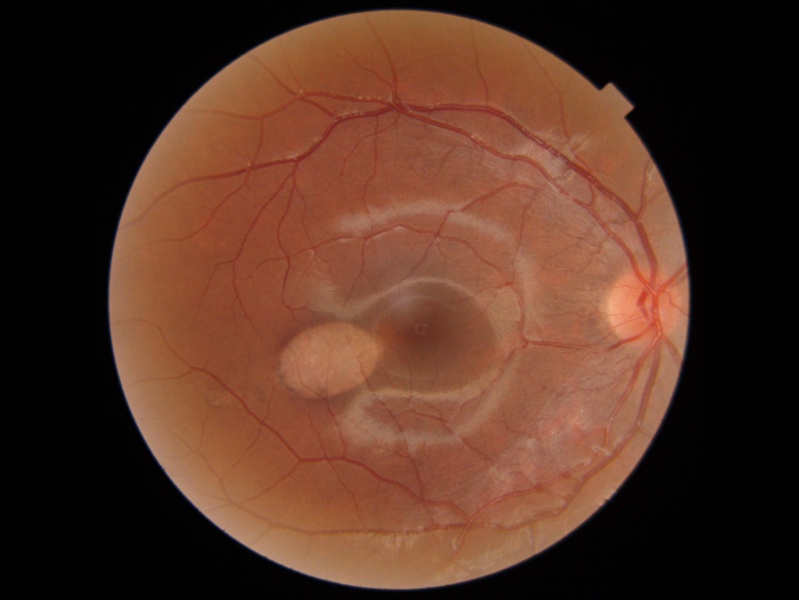

On exam, visual acuity is not generally affected since there is no foveal involvement and the lesion is usually an incidental finding. Nevertheless, central scotoma or microscotoma may be present at diagnosis. It is typically unilateral, flat, asymptomatic and non-progressive, although bilateral, crescent and satellite lesions have also been reported [3] [10] [11][12]. Furthermore, an association with neurosensory retinal detachment or multifocal central serous chorioretinopathy has been published [13][14] as well as two cases with a double-torpedo lesion [15][16]. Only 8 cases have been reported in the literature of choroidal neovascularization (CNV) associated with TM, as it is typically stable [3][17] [18][19][20][21][22][23]. Six of these cases contained a choroidal excavation, which has been associated with CNV and could be the explanation over a complication of TM. [24] Owing to the RPE and outer retina damage, these lesions are susceptible to CNV development and need to be monitored[3]. There is a characteristic hypopigmented torpedo-shaped area temporal to the macula, which points to the fovea with a hyperpigmented tail. However, rare cases of globally hyperpigmented TM have been described in the literature,[25][26][27] and Jain et. al reported 1 case of TM on the inferonasal side of the disc[28]. Regardless, the typical size is about two disc diameters horizontally by one disc diameter vertically, usually without foveal involvement [29].

Clinical diagnosis

The pathognomonic lesion on funduscopic examination is solitary, hypopigmented, oval-shaped with hints of a bullet or a torpedo and a wedge-shaped tail extending peripherally and pointing toward the foveolar region along the horizontal raphe, although rare cases may be outside of the horizontal raphe but oriented along the nerve fiber layer path with the nasal apex pointing to the optic disc.[37]